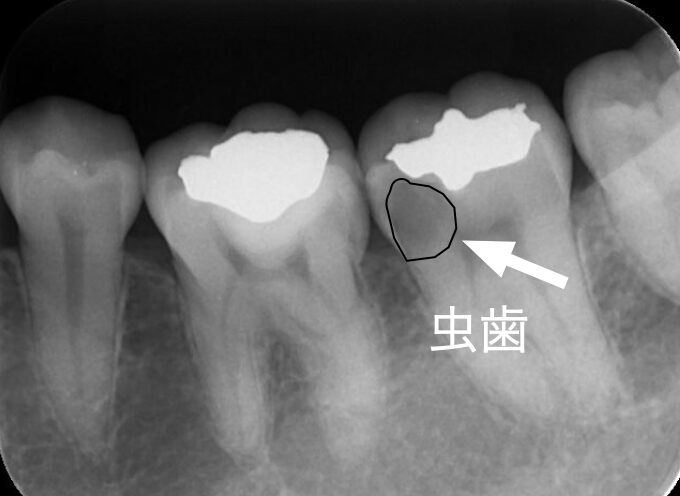

レントゲンで虫歯が確認できた。

根管治療を行い、セラミッククラウンSET。